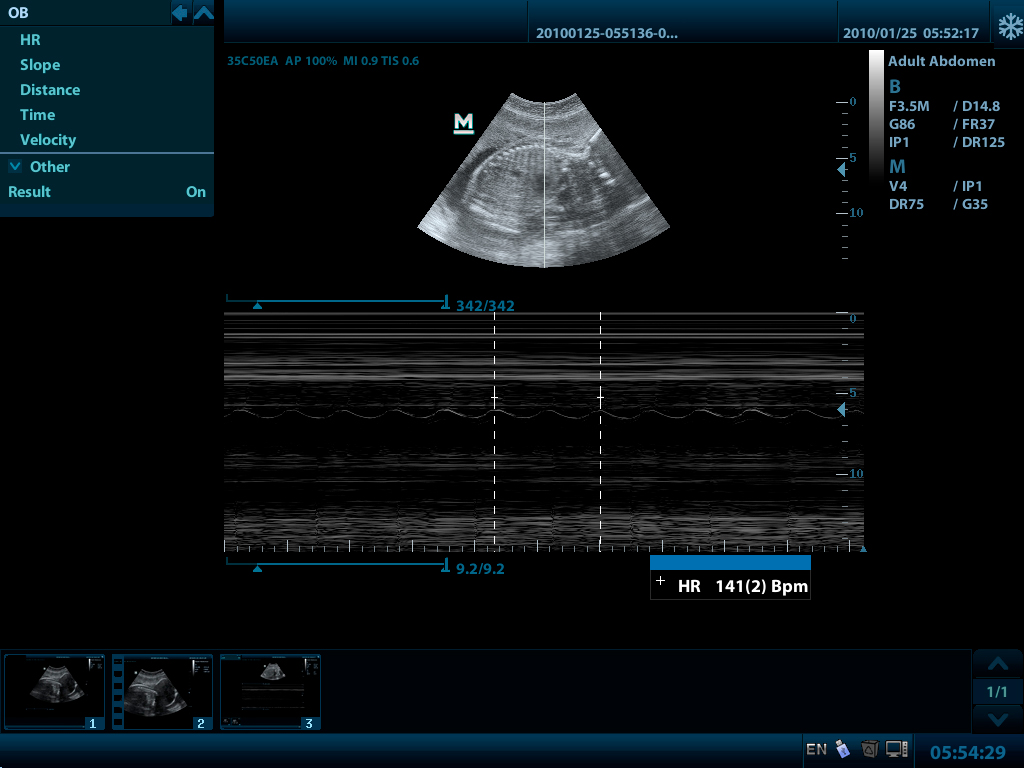

- PW Импульсно-волновой допплер с автоматической трассировкой спектра

- Режимы сканирования 2D: B/2B/4B/M/B+M